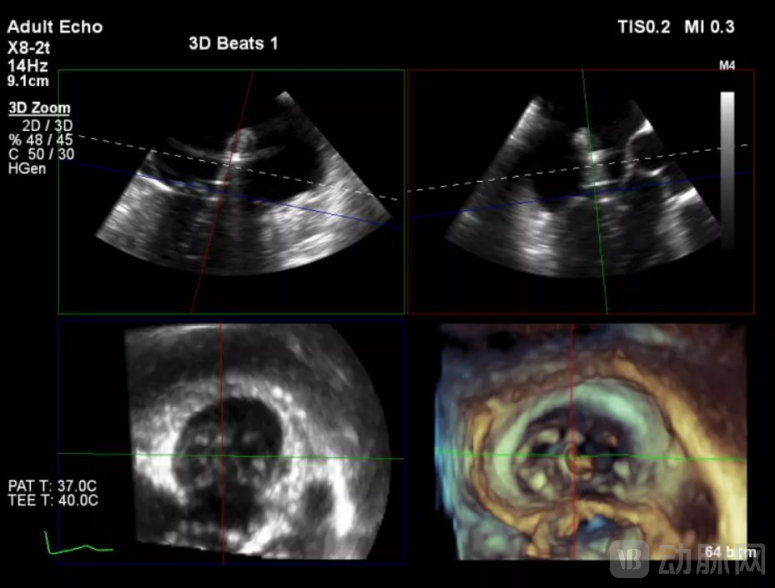

经过云南阜外医院结构性心脏病MDT团队综合讨论评估该患者病情后,患者为传统手术高危患者,瓣膜病变解剖无法行介入修复,决定进行MitraFix™经心尖二尖瓣植入。术前心脏CTA二尖瓣D形瓣环面积折算直径34mm, 模拟植入34号介入二尖瓣膜(外经约40mm)后左心室NeoLOVT面积可(>150mm2)。手术在单纯超声引导下完成,采用左侧肋间4cm微创切口心尖入路,在超声引导下,输送系统准确跨瓣,并将瓣膜准确释放于二尖瓣瓣瓣环,瓣膜释放后支架贴合牢固,无瓣周漏及瓣内反流,二尖瓣前向血流通畅,平均压力阶差2mmHg,左心室流出道通畅,流出到血流速度为2.3m/s,平均压力阶差8mmHg。顺利撤出输送系统,关闭心尖切口,手术顺利结束。

(采用3D实施多平面定位引导瓣膜释放)